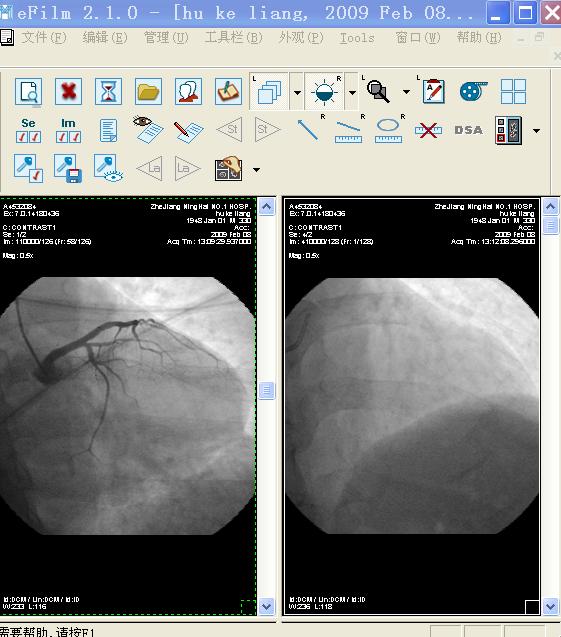

我又尝试用这两个软件打开同一个DSA文件,都可以正常显示

TT截图未命名1.jpg

TT截图未命名2.jpg

TT截图未命名3.jpg